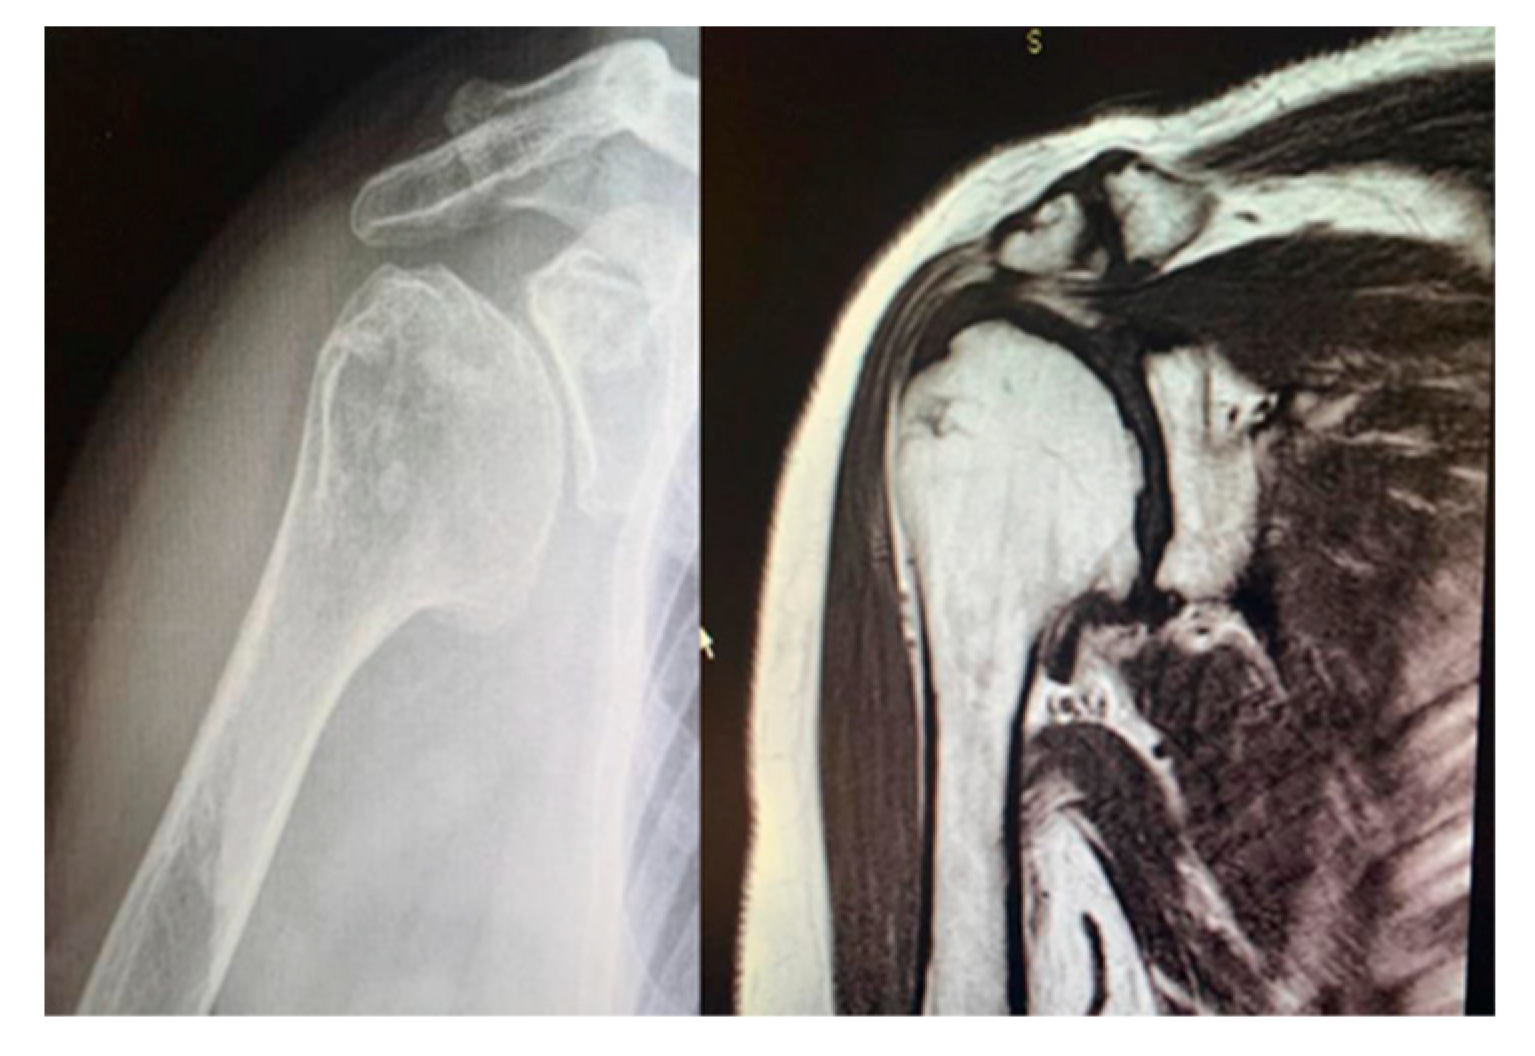

Figure 3. Pre-operative magnetic resonance imaging to evaluate the integrity of the rotator cuff and the correct indication for a HRA.

Study design. A retrospective and observational study was performed. Inclusion criteria were as follows: patients with (1) a diagnosis of concentric glenohumeral degeneration (Figure 1) with rotator cuff integrity following primary OA or RA or humeral head AVN (Figure 2), (2) glenoid articular surface type A1 or A2, according to Walch’s classification, (3) more than 60% residual humeral head, [2, 3] (4) who underwent HRA.

Surgical procedure. All the surgeries were performed by the senior Author (S.G.), implanting a Durom Shoulder Cup (Zimmer Biomet, Warsaw, Indiana, USA), a Copeland Humeral Resurfacing Head Surgery (Zimmer Biomet, Warsaw, Indiana, USA) or a SMR Resurfacing Shoulder Prosthesis System (Lima Corporate, Udine, Italy). All patients were pre-operatively evaluated through a clinical examination, plain radiographs in antero-posterior and axillay view, computed tomography scan and magnetic resonance imaging (Figure 3) in order to determine the correct indication to HRA.